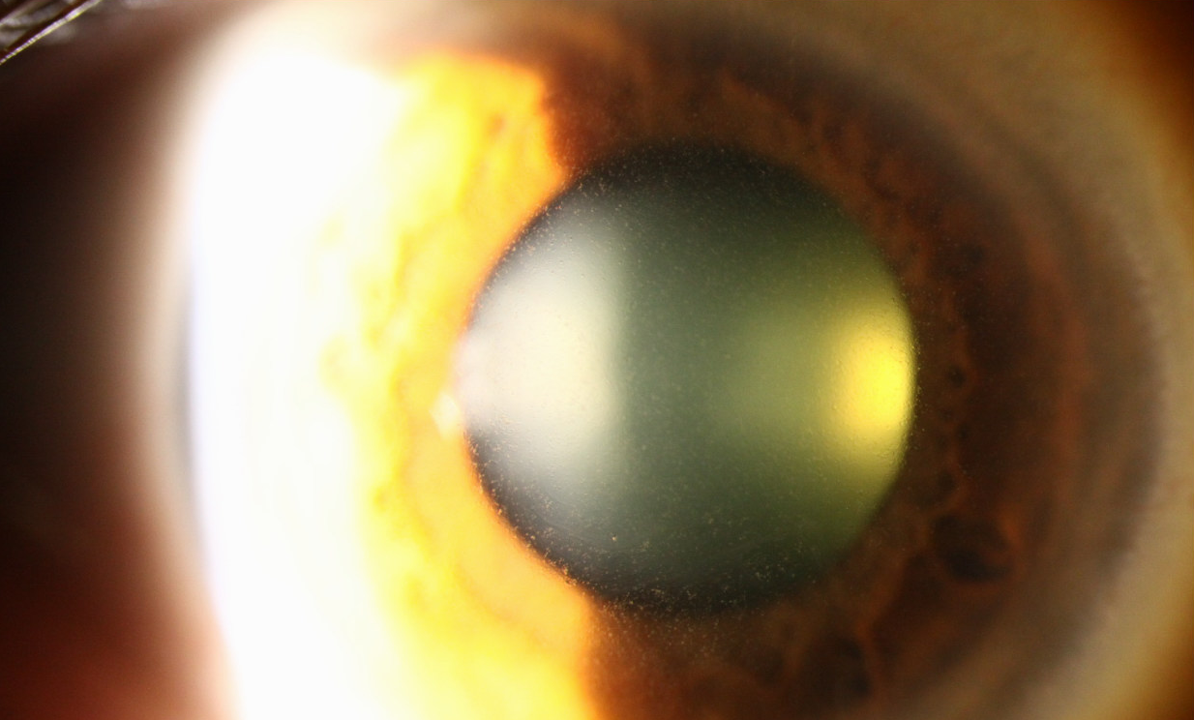

세극등 현미경 검사(slit-lamp examination) 에서 각막 낭포를 확인할수 있으며,

눈꺼풀 틈새사이 각막에서 크기, 모양이 균일하고,

형광물질에 염색되지 않는 무색 혹은 회백색의 낭포가 보입니다.